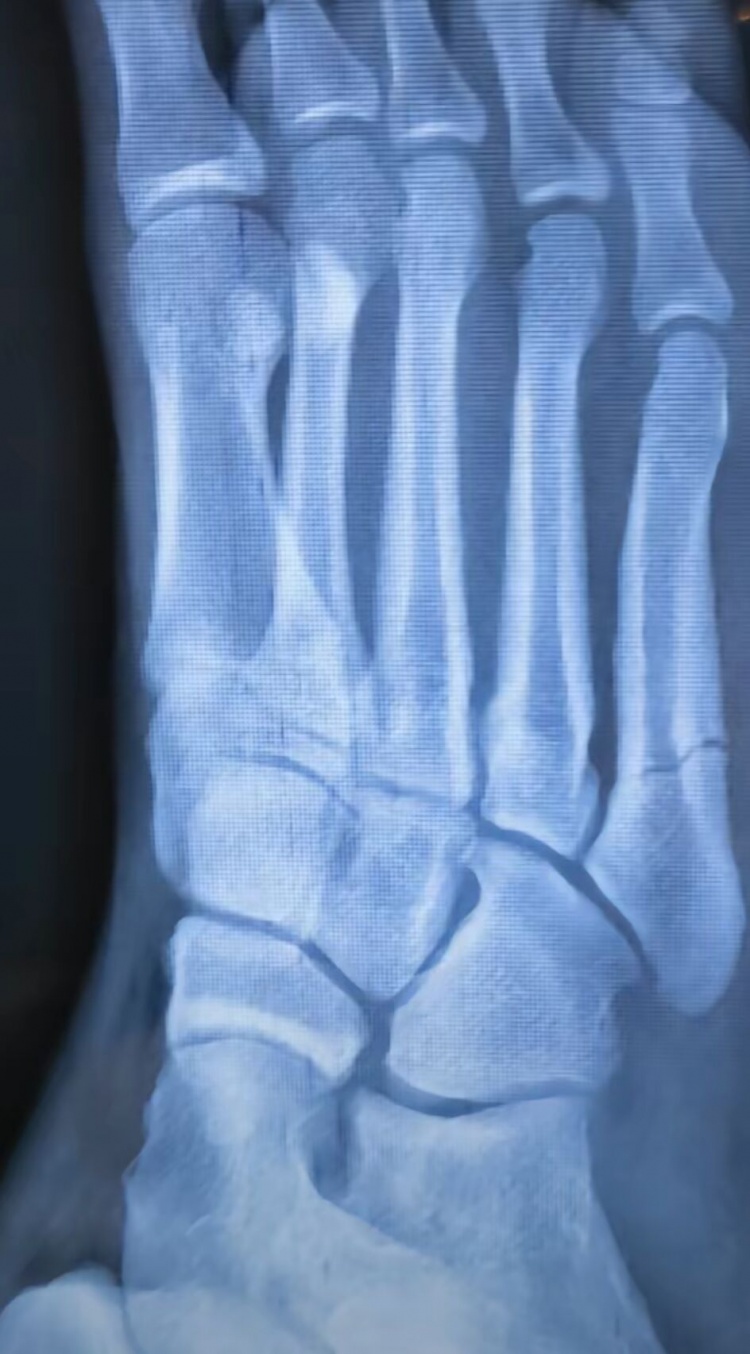

近期经过检查,蒯纪闻确诊为第5跖骨骨折,他也因此退出了U19国青的集训。

蒯纪闻在社媒晒出了他的诊断报告,并在社媒回应写道:“谢谢大家的关心,后续我会积极的康复治疗,可能会缺席一段时间。今年真是不太顺利的一年,我们下半年见。”